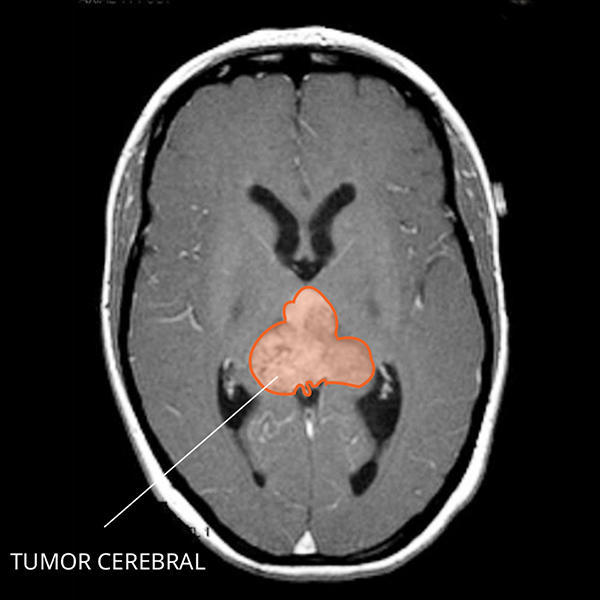

Imagen por resonancia magnética (IRM) del tumor teratoide rabdoide atípico en el cerebro.

¿Cómo se ve un TTRA en las imágenes por resonancia magnética?

El TTRA suele ser un tumor muy grande con áreas llenas de líquido que brillan cuando se usa contraste. Con frecuencia se ven áreas de sangrado o necrosis (tejido muerto).